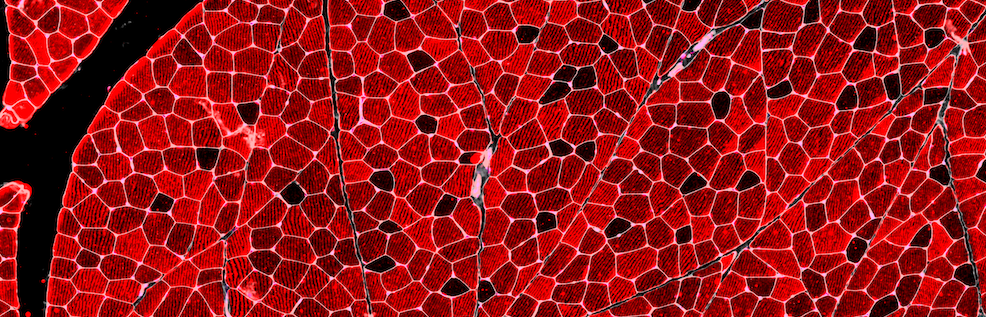

Launched in 2025, the Dyno-bn8 vector enables therapeutic delivery to skeletal and cardiac muscles at IV doses as low as 5e12 vg/kg, dramatically improving safety for muscle and neuromuscular gene therapies.

Launched in 2025, the Dyno-3hv vector is the first capsid optimized for highly efficient delivery to the multiple tissues affected by neuromuscular disorders, including the heart, skeletal muscle and CNS.